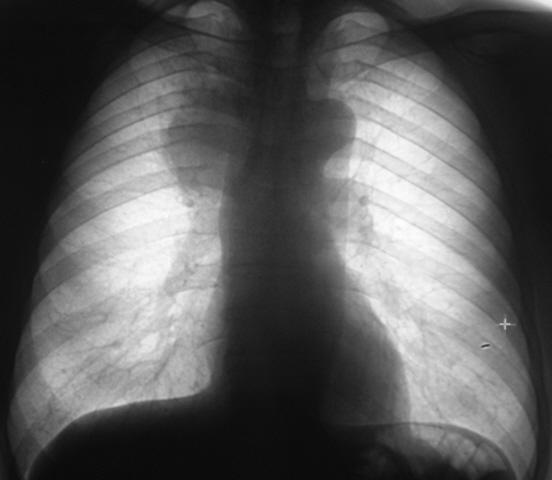

Пол пациента: Мужской пол Тип патологии: Злокачественное новообразование Область исследования: Грудная клетка и верхние дыхательные пути Методы исследования: Rg При расшифровке цифровых флюорограмм пациент взят на контроль. Приводится цифровая флюорограмма и фрагмент с увеличением изображения. Ваше мнение коллеги? Пт, 26/06/2009 - 19:45 #1 Ермолаев Не на сайте Был на сайте: 8 лет 10 месяцев назад Зарегистрирован: 07.02.2009 - 16:33 Публикации: 670 Валентин Львович! Пожалуйста, выложите боковой снимок, если таковой имеется. Объемное образование средостения. Важно в дифдиагностике, какая локализация. Переднее или заднее средостение. dok Пт, 26/06/2009 - 19:57 #2 Катенёв Валенти... Не на сайте Был на сайте: 7 лет 2 недели назад Зарегистрирован: 22.03.2008 - 22:15 Публикации: 54876 Рентгенография и томография. Пт, 26/06/2009 - 20:15 #3 Ермолаев Не на сайте Был на сайте: 8 лет 10 месяцев назад Зарегистрирован: 07.02.2009 - 16:33 Публикации: 670 Валентин Львович! Виноват, образование внутри легочное (правило Ленка). Контуры неровные, нечеткие, "лучистые". Выражена дорожка к корню легкого. Объем? dok Пнд, 29/06/2009 - 14:57 #4 Катенёв Валенти... Не на сайте Был на сайте: 7 лет 2 недели назад Зарегистрирован: 22.03.2008 - 22:15 Публикации: 54876 Пациента прооперировали. Предварительно рак лёгкого. Произвели правостороннюю пульмонэктомию.

Валентин Львович! Виноват, образование внутри легочное (правило Ленка). Контуры неровные, нечеткие, "лучистые". Выражена дорожка к корню легкого. Объем?

Пациента прооперировали. Предварительно рак лёгкого. Произвели правостороннюю пульмонэктомию.